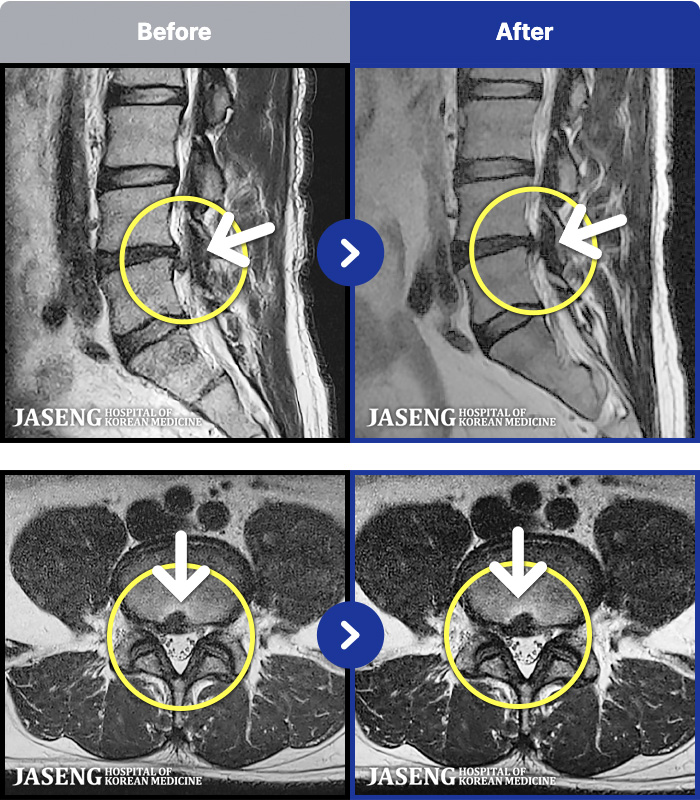

1,293 MRI ũ ʸ Ȯϼ.